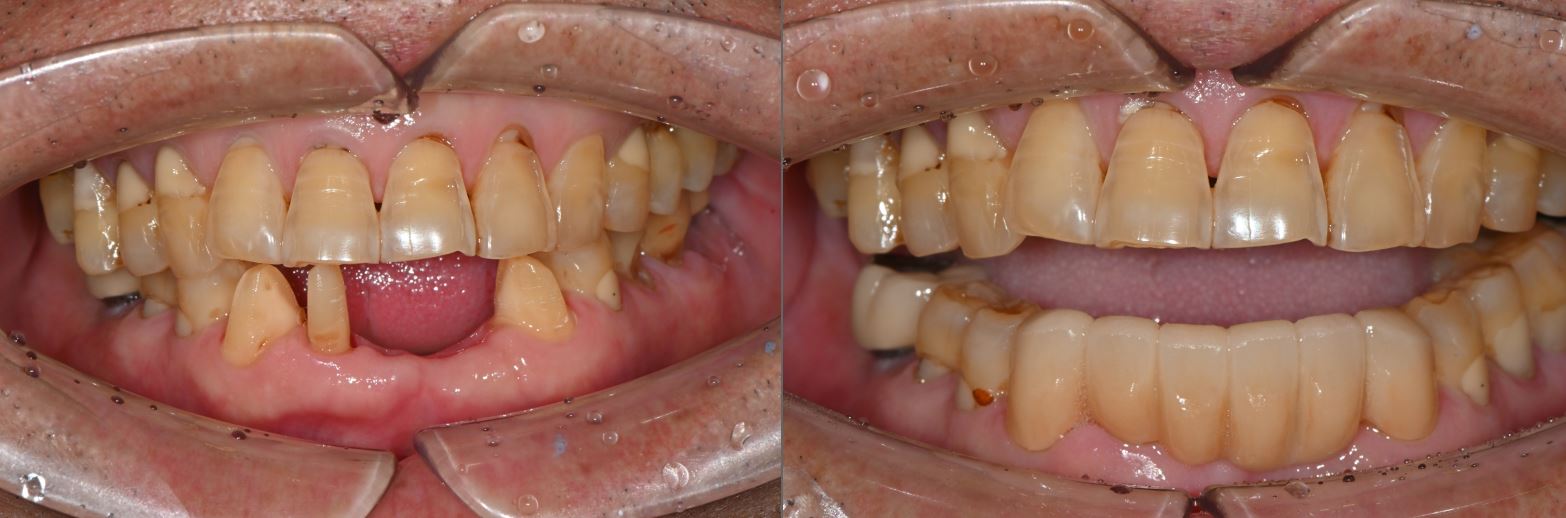

치료전후사진